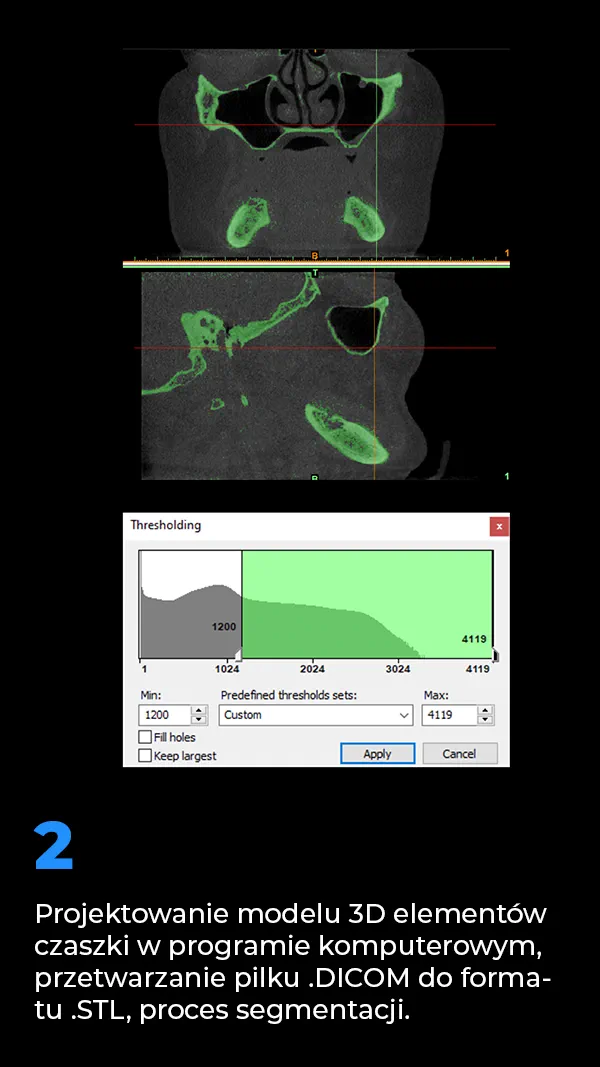

4. Schemat wytwarzania indywidualnych implantów podokostnowych

Schemat wytwarzania indywidualnych implantów podokosnowych MaiImplants.